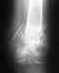

закритий двухкисточковыйп ерелом косточек правой голени с смещением,и частичное повреждение дистального межголеньего синдесмоза с подвывихом ступнин

1 неделя гипс,повторный снимок,направление на операцию,через неделю операция,гипс 8 недель,сняли 3 дня назад , вставать не в состоянии,двигать ступней тоже нереально....

нога отекла ,как у слона , подскажите правильно ли все сделано , нормальное ли состояние на сегоднешний день, и сколько нужно времени, чтобы ходить хотя бы с палочкой, какие упражнения? врач сказал: массаж не нужно, парить только ногу и потехоньку ее нагружать..снимок прилагаю

Проблем больших не видно. Нужно разрабатывать движения. В качестве образца - здоровая нога. Надо именно разрабатывать. Частичная нагрузка возможна. Будете ее увеличивать по мере спадения отека.